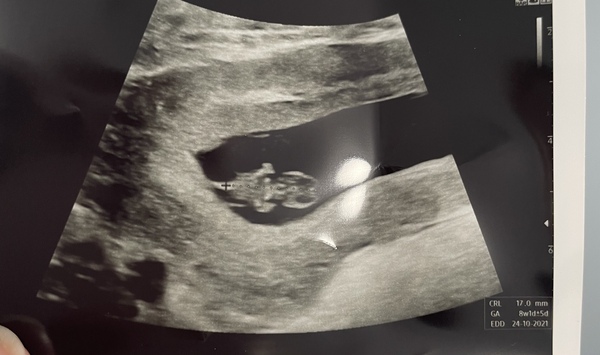

Strawberry08 · 15/03/2021 09:22

All good!! So so pleased. Measuring bang on 8+1 which is the same as my LMP. Everything looks great.

Just a shame the scan looks like a lizard 😂😂

@Strawberry08 so happy for you. Great pic - do you think that's looking at the back of the baby lying on it's side?